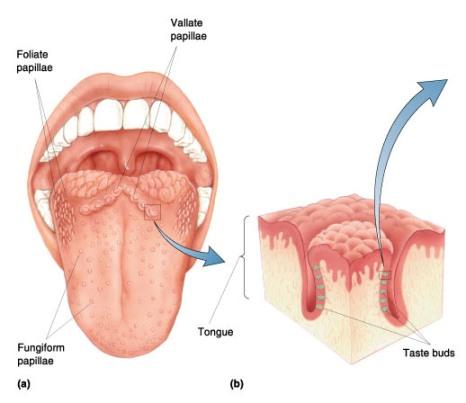

Taste bud

28

Frenulum

29

Papullae

30

Filiform

Papillae

31

Fungiform

Papillae

32

Circumvallate

Papillae